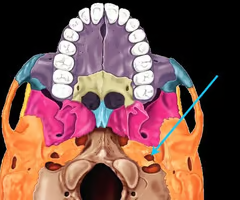

Palatine process of maxilla (helps form hard palate with palatine bones)

Palatine bones

Vomer

Vomer

Occipital condyles (articulates with superior articular surfaces of atlas)

Foramen magnum (“big hole” for the spinal cord)

Carotid canal (for internal carotid artery)

Jugular foramen (for internal jugular vein and nerves)

Pterygoid processes of sphenoid bone (trough - shaped anchor for chewing muscles)